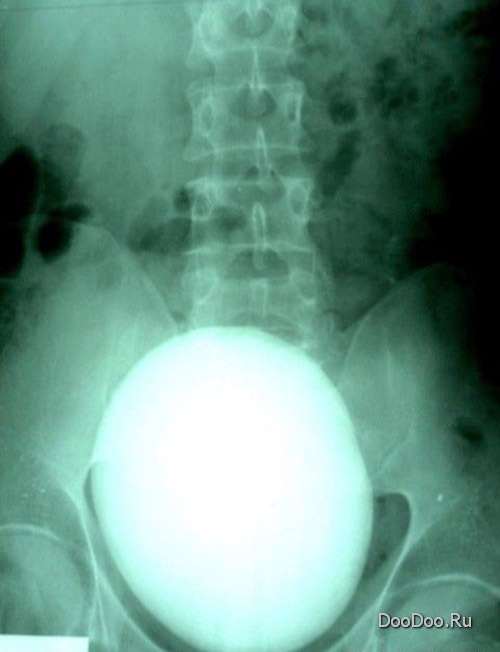

Это почечный камень весом в 700 гр., удаленный в Венгрии у г-на Шандора Сардаки.

Камень был обнаружен случайно, при проведении рентгеновского исследования.

Диаметр камня - 17 см.